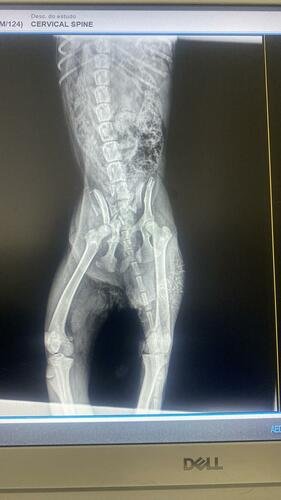

Movido pela compaixão, corri até o local, e com a ajuda de bons corações, consegui resgatá-la a tempo. Imediatamente, a levei ao veterinário, onde descobrimos a extensão de suas lesões. Seu pequeno corpo está marcado por múltiplas lesões na região da Pelve (popularmente chamada de Bacia), e para que ela tenha uma chance de uma vida plena novamente, é crucial que ela passe por uma cirurgia urgente.

RAIO-X

Documentos comprobatórios: